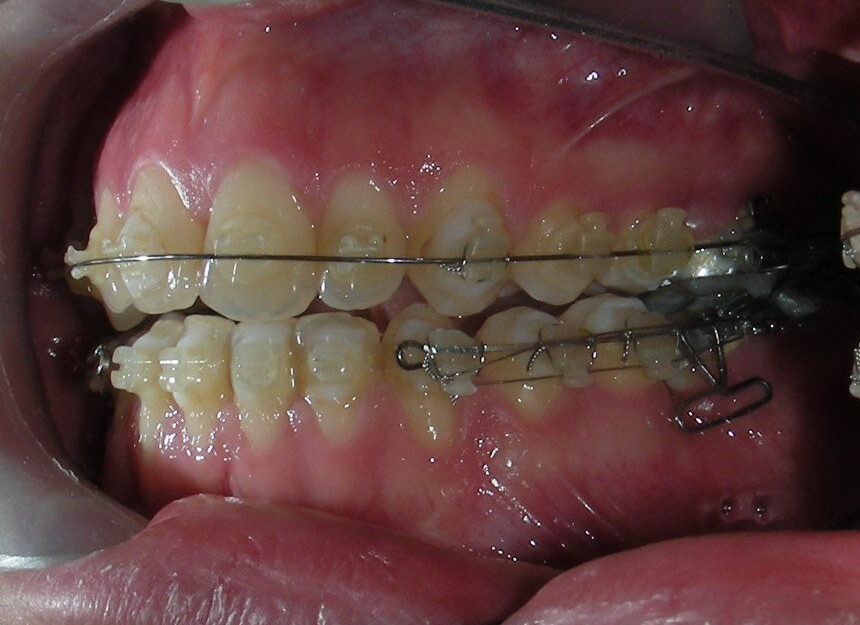

The upper brackets were bonded solely for the purpose of providing stability to the utility arch . Following the hierarchically structured treatment plan, we proceed with the alignment and leveling phase in order to enable mesialization of the posterior segments using sliding mechanics, which works effectively in conjunction with Roth prescription brackets .022.

A progressive archwire sequence was used for alignment, leveling, and three-dimensional control.

-

.014″ NiTi round wire

.016″ NiTi round wire

.016″ × .022″ NiTi rectangular wire

- .018″ × .018″ Blue Elgiloy sectional archwire was placed in three segments in the maxillary arch to maximize the effectiveness of Class II intermaxillary elastics, in conjunction with space closure (mesialization) in the mandibular arch.

- 017″ × .025″ Blue Elgiloy sectional leveling archwire beetwen # 35-37 and 45-47

- 017″ × .025″ Stainless Steel (SS) + Closed-coil NiTi springs were activated between the molars and anterior segment

- 019″ × .025″ Stainless Steel (SS)

After two years of treatment using appropriate biomechanics, the overbite was successfully corrected from -8 mm to +1 mm, achieving complete closure of the anterior open bite without exacerbating the patient’s lower facial third vertical proportions. At this stage, occlusal contacts were verified using articulating paper, and functional movements of the canines and incisors were evaluated to ensure proper anterior guidance and disclusion patterns. The patient was then referred to speech therapy (myofunctional evaluation) as part of the pre-debond assessment protocol.